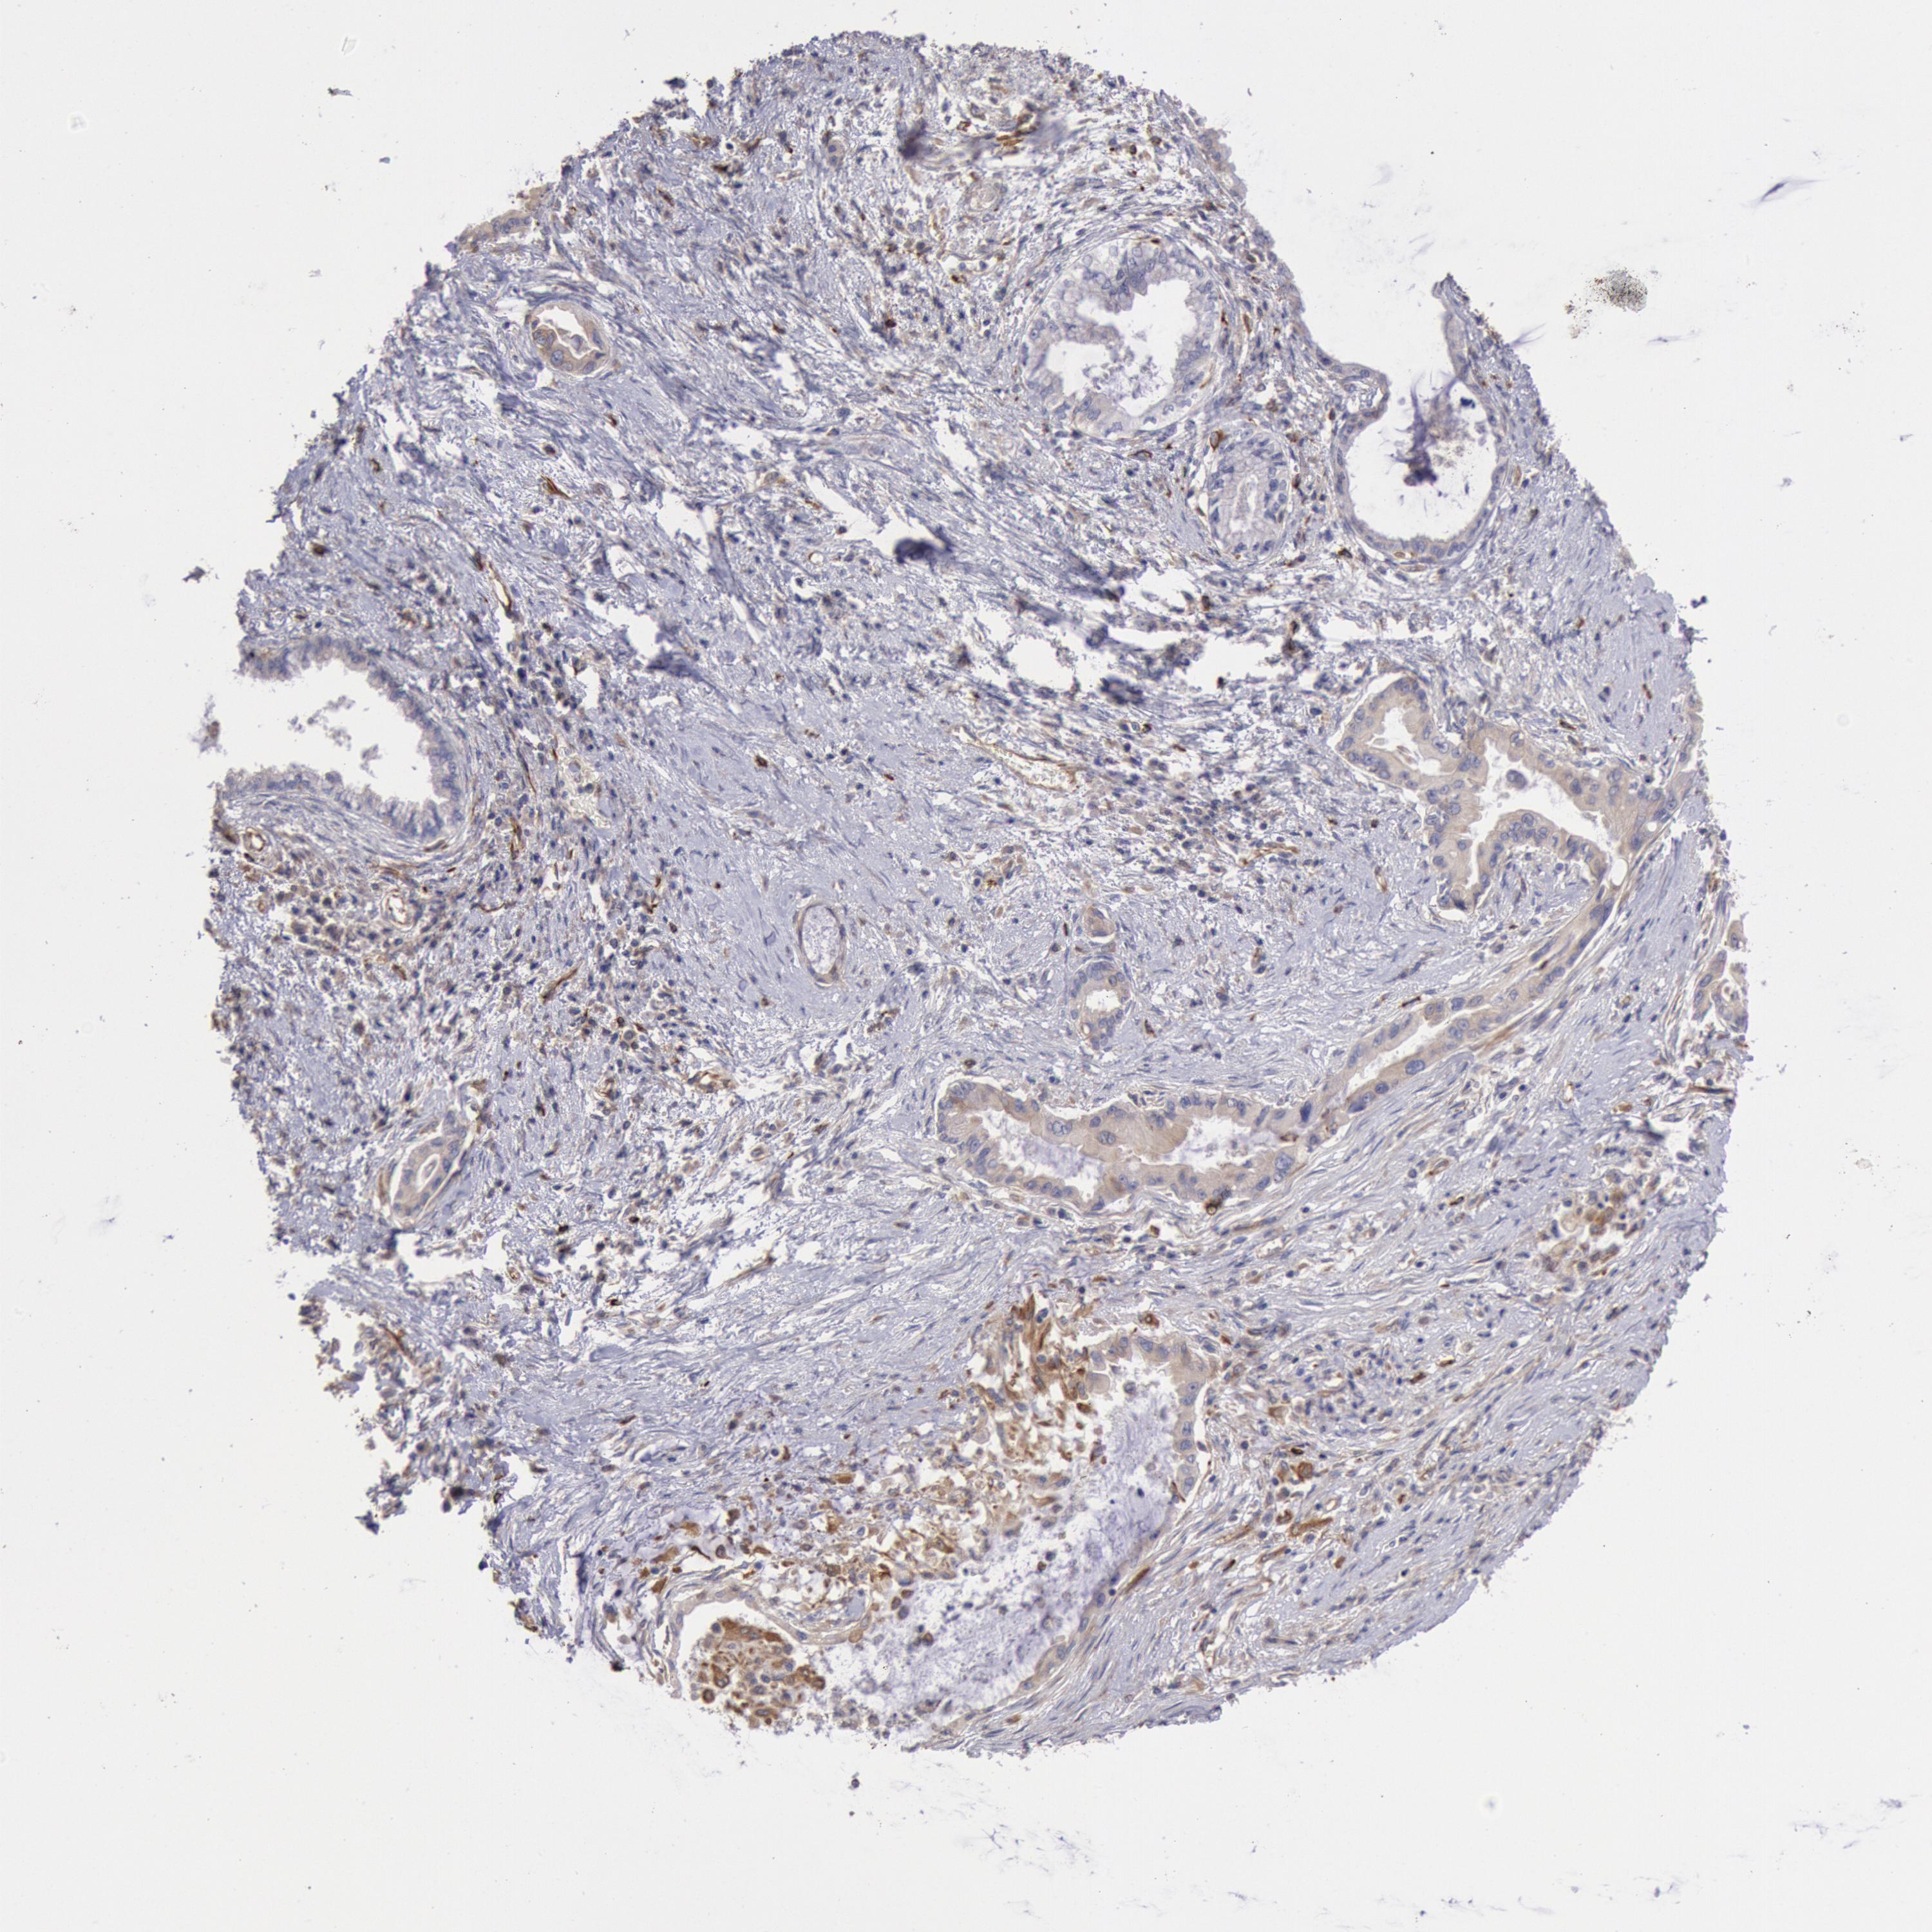

PANCREATIC CANCER - Protein expressioni

A mouse-over function shows sample information and annotation data. Click on an image to view it in a full screen mode. Samples can be filtered based on level of antibody staining by selecting one or several of the following categories: high, medium, low and not detected. The assay and annotation is described here.

Note that samples used for immunohistochemistry by the Human Protein Atlas do not correspond to samples in the TCGA dataset.

Antibody stainingi

Antibody staining in the annotated cell types in the current human tissue is reported as not detected, low, medium, or high, based on conventional immunohistochemistry profiling in selected tissues. This score is based on the combination of the staining intensity and fraction of stained cells.

Each image is clickable and will lead to virtual microscopy that enables deeper exploration of all samples and also displays staining intensity scores, fraction scores and subcellular localization as well as patient and tissue information for each sample.

Antibody HPA001202

Staining

High

Medium

Low

Not detected

Intensity

Strong

Moderate

Weak

Negative

Quantity

>75%

75%-25%

<25%

None

Location

Nuclear

Cytoplasmic/membranous

Cytoplasmic/membranous,nuclear

Adenocarcinoma, NOS